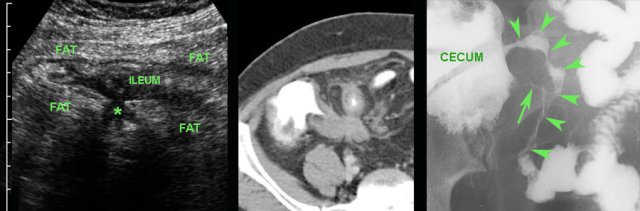

Air in the lumen can make it difficult to identify the inflamed appendix (arrowheads).

The echolucent wall and the surrounding inflamed fat (*), make clear that appendicitis is present.

In this 16 year old patient with RLQ pain, enlarged mesenteric lymph nodes surrounded by some inflamed fat (*) were the only US finding and the appendix could not be identified.

CT confirmed the enlarged nodes (arrowheads), but revealed an inflamed appendix (arrow), originating from the cecum in deep pelvic position.

Young patients with acute appendicitis often have secondarily enlarged mesenteric lymph nodes.

In this young man with suspected appendicitis both ileum and appendix (arrow) were thickened, due to ileocecal Crohn disease, also affecting the appendix.

Barium study confirms Crohn ileitis and shows irregular filling of the appendix, proving that this is a case of non-obstructive Crohn appendicitis.

Variable involvement of the appendix (arrow) in ileocecal Crohn disease:

- No involvement (left),

- Slight involvement (arrowhead) (middle)

- Severe involvement, with abundant inflamed fat * (right)